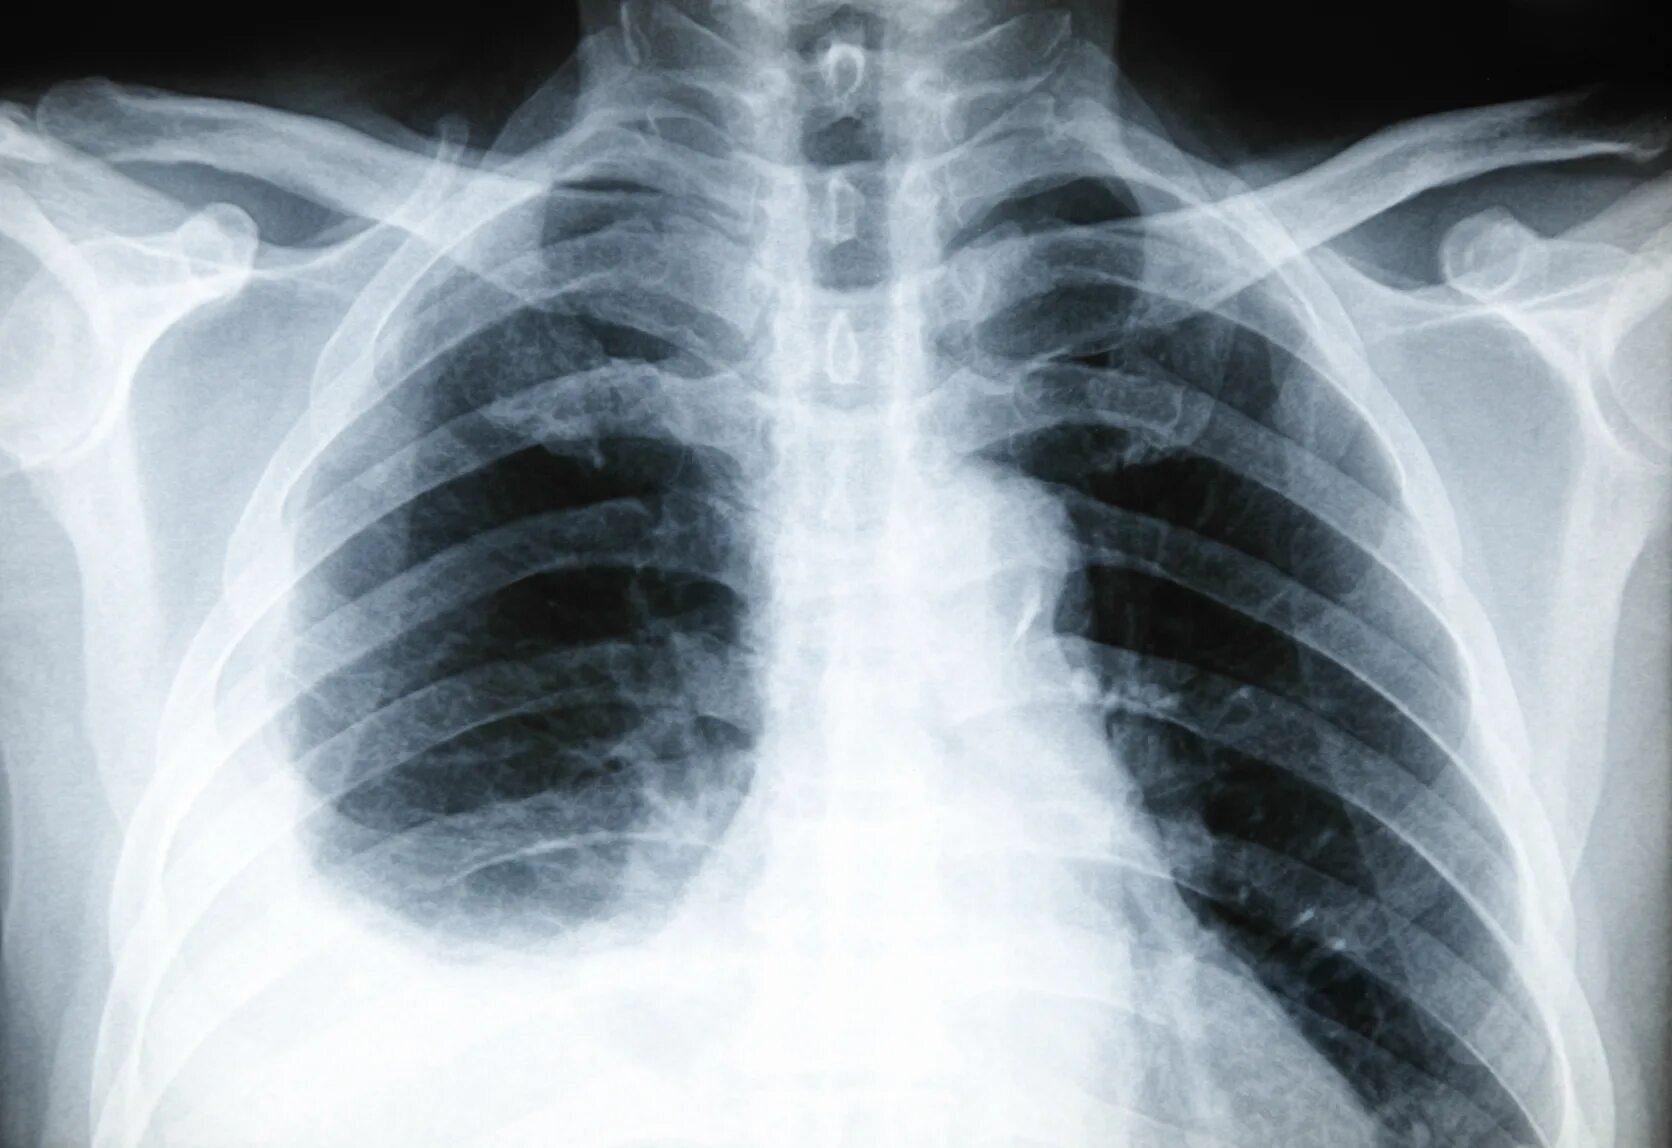

• Рентгенография грудной клетки – позволяет выявить выпот в плевральной полости или другие изменения